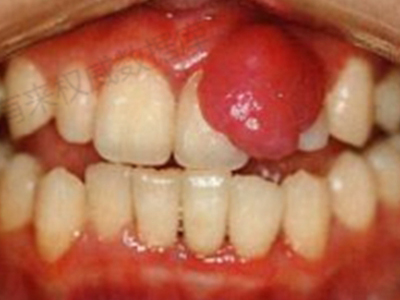

牙龈瘤是指发生在龈乳头部位的炎症反应性瘤样增生物,好发于女性,前磨牙区最为常见。牙龈瘤来源于牙周膜及牙龈的结缔组织,因其无肿瘤的生物学特征和结构,故非真性肿瘤,但切除后易复发,因此切除务必彻底,必要时拔除相关牙齿。

牙龈瘤多发于女性,以青年及中年人为常见,多发生于牙龈乳头部,位于唇、颊侧者较舌、腭侧者多,最常见的部位是前磨牙区。肿块较局限,呈圆形或椭圆形,有时呈分叶状,大小不一,直径由几毫米至数厘米。

肿块有的有蒂,如息肉状;有的无蒂,基底宽广,生长较慢,但在女性妊娠期间可能迅速增大。较大的肿块可以遮盖一部分牙及牙槽突,表面可见牙压痕,易被咬伤而发生溃疡,伴发感染。随着肿块的增长,牙槽骨壁逐渐被破坏,牙可能发生松动、移位。